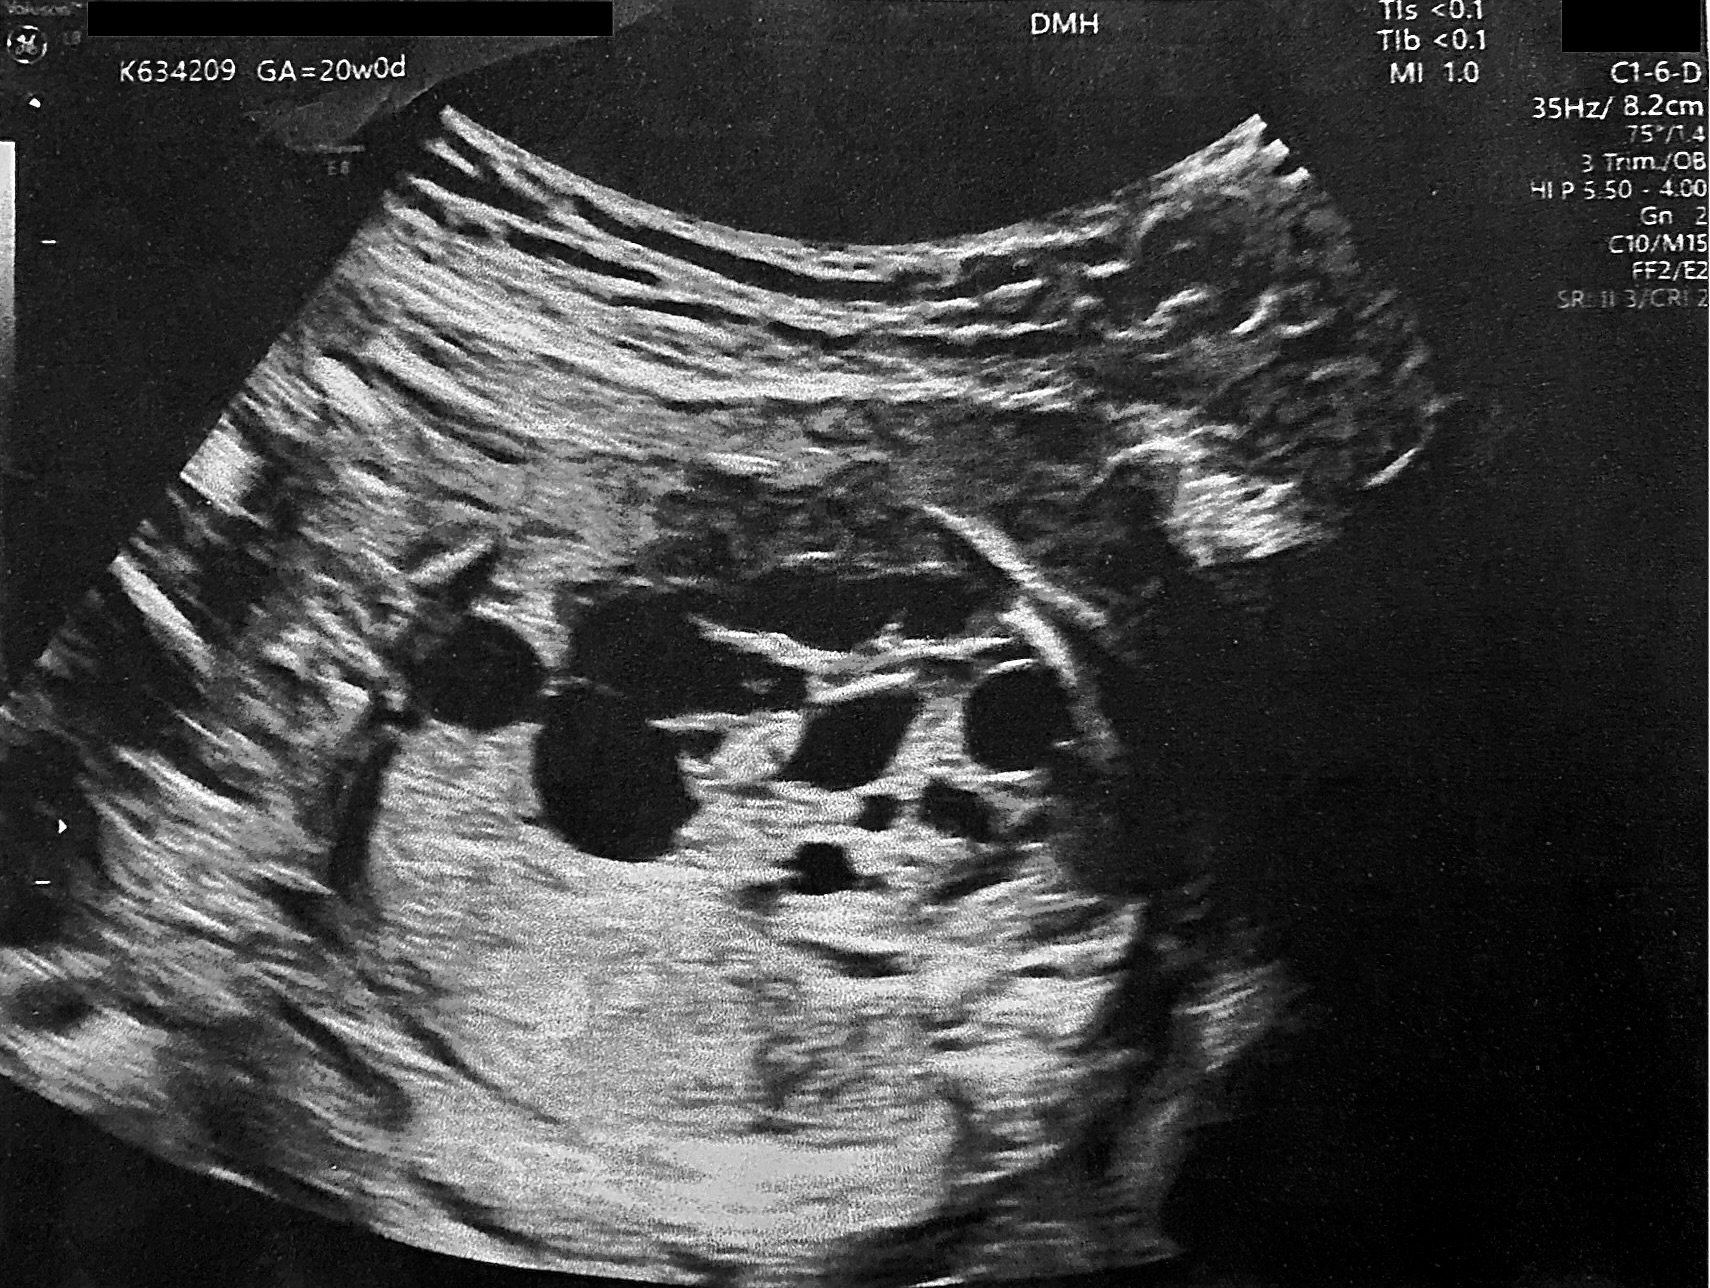

Preterm premature rupture of membranes (pPROM) before 22–24 weeks of gestation is considered previable and poses a high risk to the chances of successful delivery. Multicystic dysplastic kidney (MCDK) is the most common form of dysplasia of this organ, usually affecting 1 kidney. A prenatal suspicion of MCDK requires escalation of the clinical process to a reference center qualified and equipped for further diagnosis and treatment. We present a unique case of prenatal pPROM at 19 weeks of gestation in a pregnancy complicated by fetal MCDK as an interesting obstetric and neonatal patient story. We have not found any published evidence on the impact of coexisting fetal congenital malformations on a pregnancy affected by previable pPROM.

Ji H, Dong SZ. Magnetic resonance imaging for evaluation of foetal multicystic dysplastic kidney. Eur J Radiol 2018;108:128-32.

Balasundaram M, Chock VY, Wu HY, Blumenfeld YJ, Hintz SR. Predictors of poor neonatal outcomes in prenatally diagnosed multicystic dysplastic kidney disease. J Perinatol 2018;38(6):658-64.